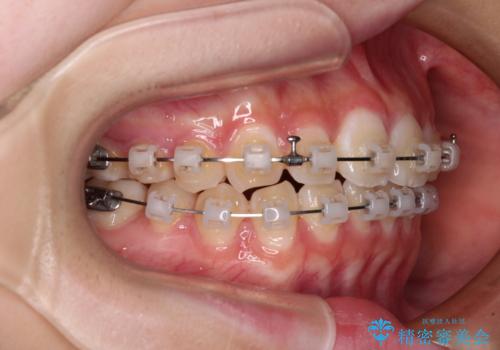

- 矯正装置

- クリアブラケット

- 治療期間

- 11ヶ月